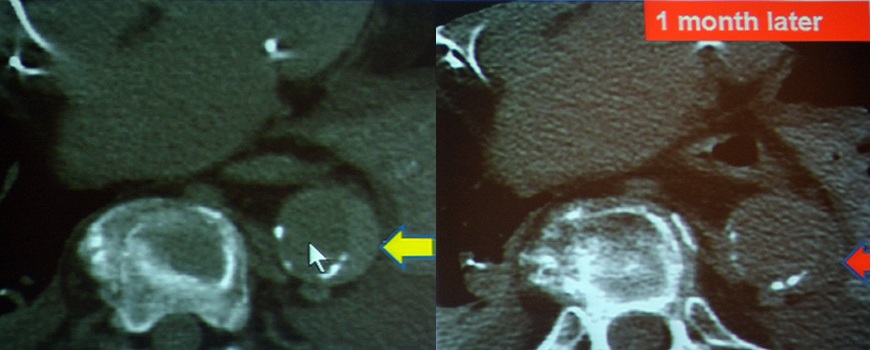

急性主动脉综合征:包括主动脉夹层、壁间血肿、穿透性溃疡。TRO可发现主动脉夹层的真假腔和内膜片。

图10-11 壁间血肿